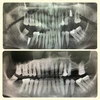

الدكتورة سيفيم شاكيليطاش طبيبة أسنان

مجالات التخصص

طب الأسنان